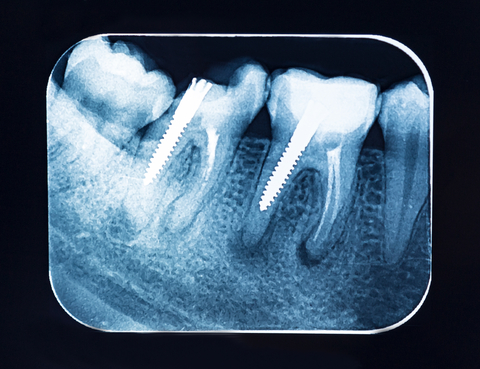

- Evaluare clinică și radiologică

- Tratament de canal (dacă nu a fost deja făcut)

- Amprentare sau alegerea unui pivot prefabricat

- Cimentarea pivotului

- Reconstrucție coronară – cu compozit sau coroană protetică